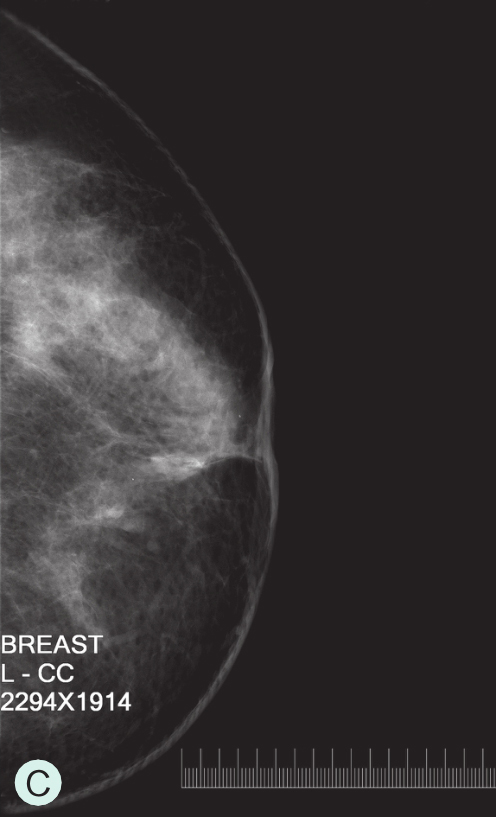

图1-3-1 乳腺X线不同乳腺密度

A.脂肪型;B.散在致密型;C.不均匀致密型;D.极度致密型

C级:不均匀致密型(可能掩盖小肿块)(图1-3-1C、图1-3-2C、图1-3-3C)。